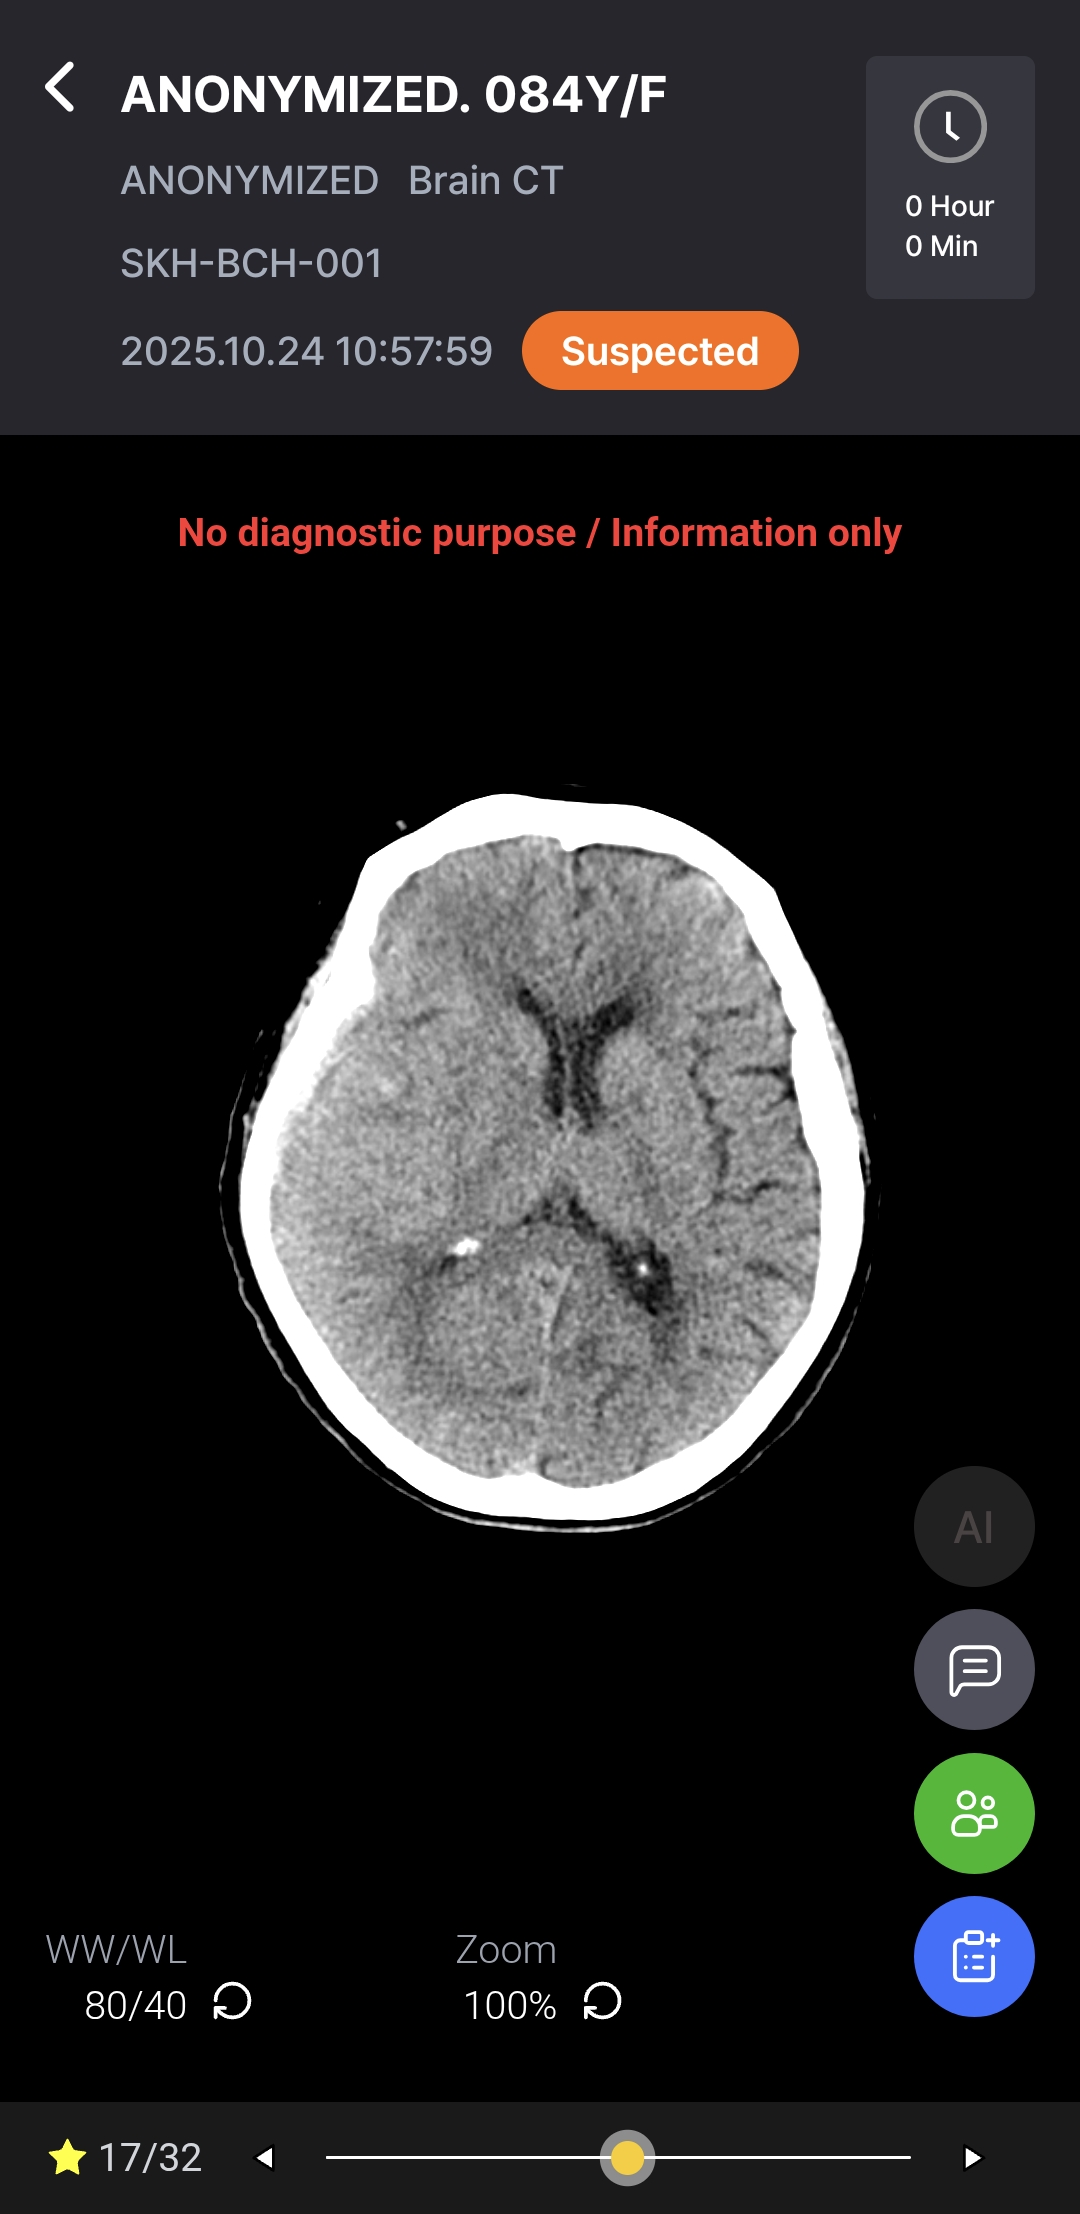

Download BrochureAI-powered diagnostic support for rapid, accurate detection and localization of brain hemorrhages on non-contrast CT, with ROI visualization and volume quantification to help radiologists assess hemorrhagic regions.

Notifications & AI DICOM Viewer

As a Radiological Computer Aided Triage And Notification Software, Hyper Insight™ – ICH functions as a triage and notification tool – supporting, not replacing, medical judgment. Final diagnosis and treatment decisions remain the responsibility of qualified medical professionals.